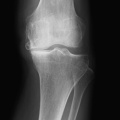

「外科」という言葉が含まれる診療科は、本来は手術をする診療科ということであって、骨折、変形性関節症、靱帯断裂、椎間板ヘルニアなど、さまざまな運動器の疾患で病院では手術が行われます。大きな病院では、専門的な手術で、部位別に特化して診療にあたりますので、外傷班、脊椎班、股関節班、膝関節班、肩肘関節班、手外科班、足の外科班、小児整形外科班などに分かれていることも少なくありません。

外来診療も手術ほど好きではないという先生もいるので、病院では「忙しい」という理由で、触診をしない、小児の症例でレントゲンを左右で比較しない、エコー検査をせずレントゲンだけで診断しようとする傾向があるかもしれません。

違う施設のケースでは、左右を比べれば同じような骨のパターンなのに、片側しかレントゲンを撮影せず、そして強い痛みでもないのに「骨折」と言われてスポーツを制限されてしまったというケースもありました。これもエコーを併用すれば急性の外傷でないことはすぐにわかったかもしれないのですが、エコーを使わない診療をすると診断が異なってしまうことがあるという一例です。